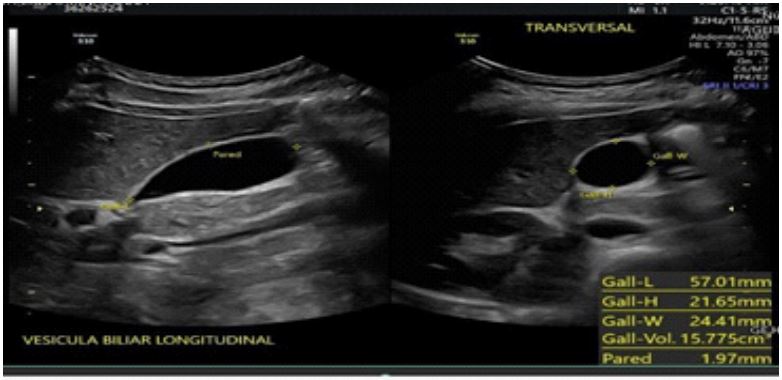

Subsequent control ultrasound reported:

- Gallbladder: Normal shape and contours, dimensions 57x21x24 mm (longitudinal, anteroposterior, transverse). Volumes: 17.7 cc. Thin wall (1.9 mm) heterogeneous due to a localized image at the body and anterior wall measuring 2x1 mm, hyperechoic, homogeneous, solid, regular contours, avascular.

Conclusion: Small polyp inside the gallbladder. No other abnormalities noted in this study (Figure 2).

Figure 2: Control ultrasound without alterations.